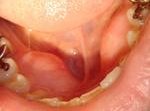

下顎骨隆起 口腔癌と間違える組織 下顎骨隆起も上顎骨隆起と同様に「もしかしてこれは?」と勘違いする骨の出っ張りです。 写真のようにひとかたまりとは限らず三つ、四つぼこぼことこぶ状にあるため以前からあったのを気がつかないで驚いて来院します。 臨床では義歯装着の障害になるためまれに除去することもありますが場所柄治癒が悪いためあまりお勧めいたしません。 関連記事 舌の良性腫瘍知歯周囲炎舌根の葉状乳頭耳下腺、顎下腺、舌下腺開口部上顎骨隆起 投稿ナビゲーション 上顎骨隆起舌の良性腫瘍